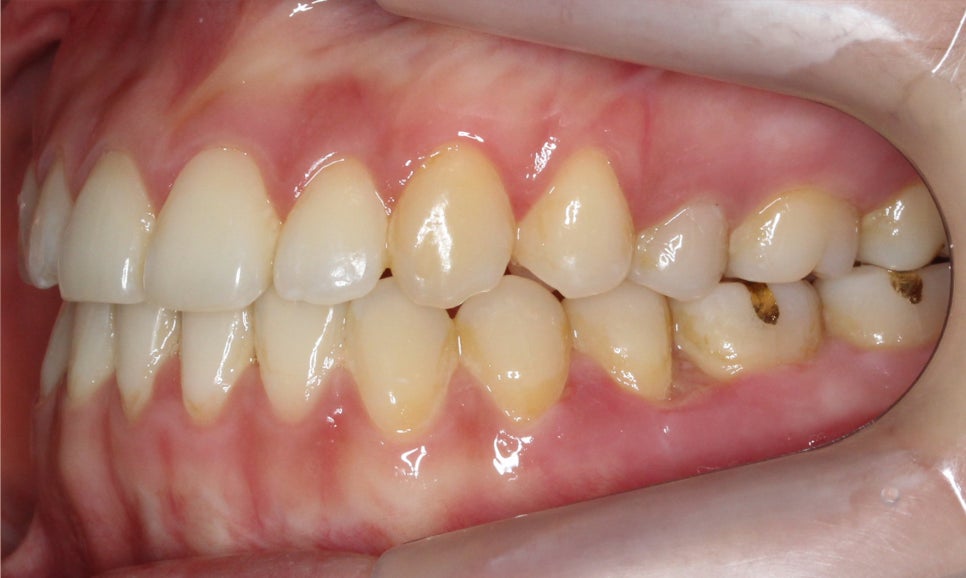

교정 후 전치부의 절단교합 증상이

많이 완화된 모습으로 overjet 사진에서

바른 교합 상태를 확인할 수 있는데요,

교합평면도 좌우 모두 클리피씨 교정 후

어금니의 교합이 바르게 교정된 모습입니다.